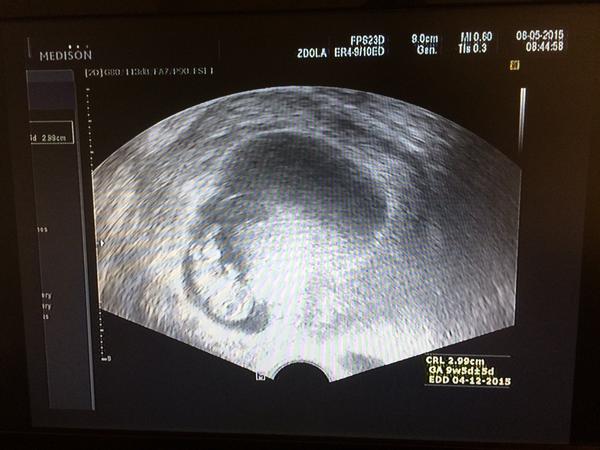

Jinak co se tyka mimi, ma se cile k svetu, v st jsem byla na utz u sve dr...mame 3cm, srdicko tluce a vse v poradku, dokonce se i hybalo, kopalo nohama a rukama hybalo 🙂 Byl se mnou manza, tak koukal jak divy, uplne slzy v ocich..jak se hybalo. Dr. mu vse vysvetlila, pak si mimi vyfotil na obrazovce a byl spokojen. Ve ct. v tom mem stavu, asi si dokazete predstavit..jsme jeli do Frydku na odber krve na 1.screening. Strasne mili byli v krevnim centru, super fakt. A ta cesta autem, ani nebudu vykladat. Pak hned zas domu do postele.

Posilam fotecku z uterka. Vypada jak ufouncek, ale jsou to pry mozkove laloky 🙂